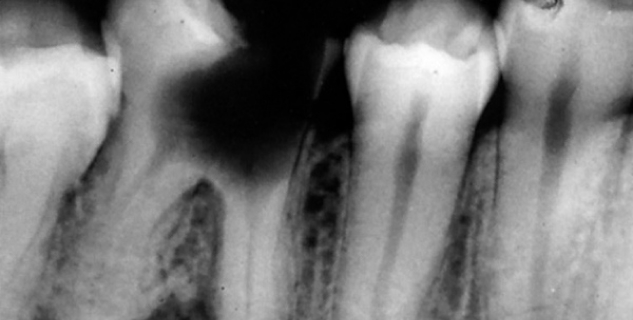

• Радиовизиограф позволяет выявить количество, длину, строение каналов, качество их прочистки, плотность заполнения пломбировочным составом.